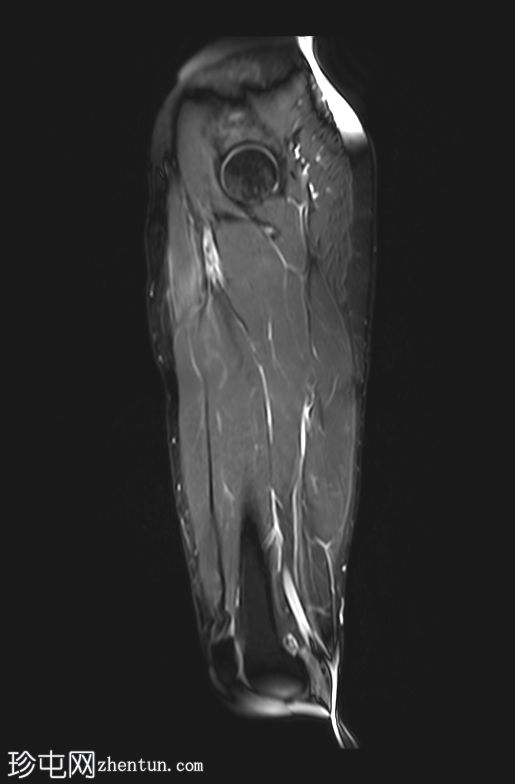

3.jpg

矢状位

T1加权像

影像显示右侧阔筋膜张肌(TFL)拉伤,伴有水肿,阔筋膜浅层受累。

右侧缝匠肌也可见轻度拉伤,肌间液在股直肌、缝匠肌和阔筋膜张肌之间流动。

此外,筋膜水肿沿髂胫束向下延伸,髂胫束是一条从髂嵴延伸至胫骨外侧的厚筋膜带。

未见局灶性纤维断裂或肉眼可见的撕裂。未见血肿。